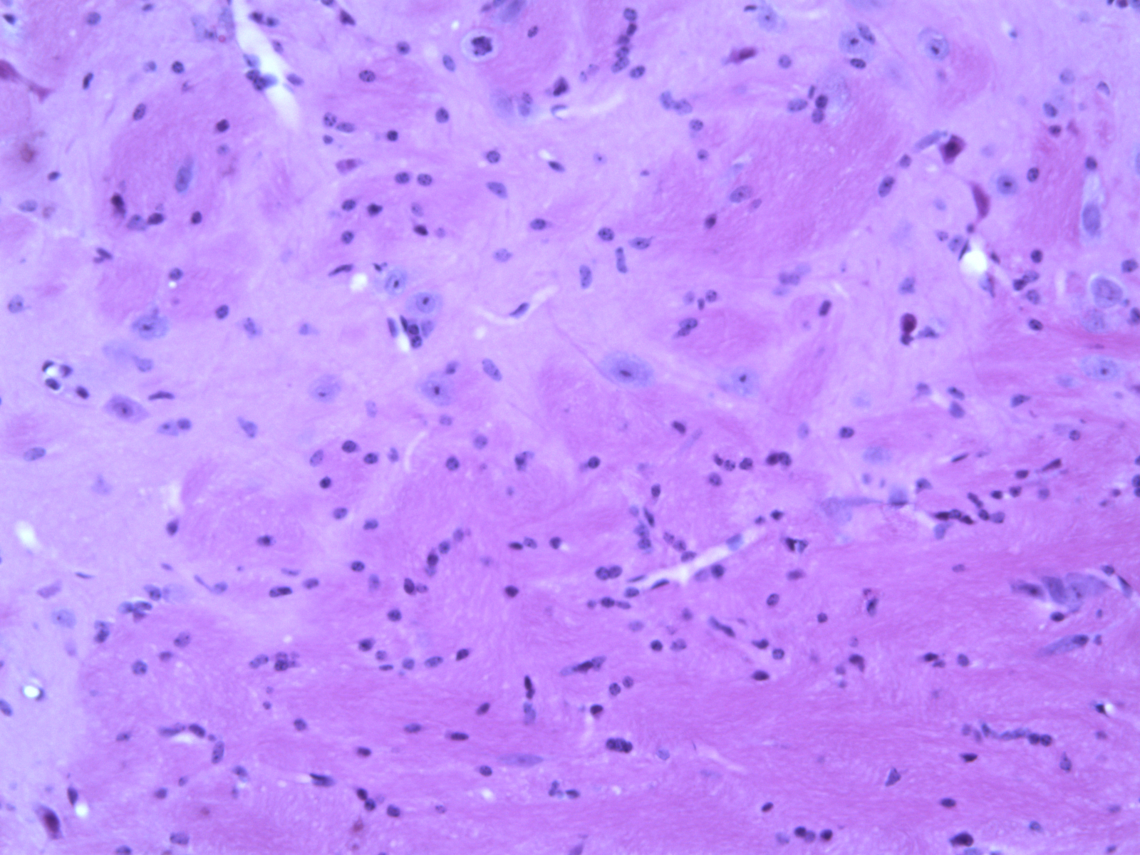

Striking Laboratory Data Images

Laboratory Data Gallery